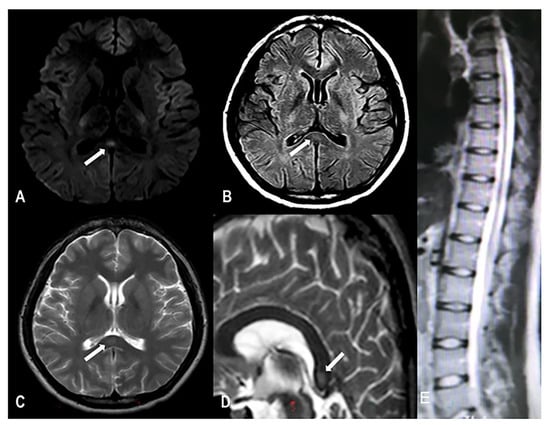

One week before the first medical examination, he had intermittent headaches, blurred vision, and difficulty falling asleep. Laboratory-test results showed that the serum vitamin B12 concentration was 227 pg/mL (normal range: 150–300 pg/mL), and fundoscopy was performed to exclude eye diseases. The initial local clinician diagnosed the mental symptoms caused by nitrous-oxide addiction. The patient was instructed to use olanzapine (2.5 mg/d) for treatment; however, the patient’s condition worsened after one week of treatment. On admission, the frequency of headaches and blurred vision was increased to more than 10 times a day. Headache was specifically manifested as forehead pain. The patient did not develop any nausea or vomiting, coma, or convulsions. The pain affected his sleep, but he could still fall asleep naturally. In addition to the needle-like pain at the end of the limbs, the patient was also accompanied by sensory disturbances in the lower limbs, mainly manifesting as hypoesthesia and impaired positional sense. The Mini-Mental State Examination (MMSE) score was 28, and the headache impact test-6 (HIT-6) score was 69 (Table 1). Muscle power in the proximal muscles of both upper and lower limbs was 5/5, muscle power of the ankle joint was 4/5, bipedal knuckle dorsiflexion was 3/5, plantar flexion was 3/5, and right tibialis anterior was 3/5. The physiological reflex was normal, and the pathologic reflex was not elicited. The finger-to-nose test was accurate and confirmed stability, and the Romberg test was negative. However, the patient found it difficult to walk in a straight line because of the reduced muscle strength in the right lower limb. The electroencephalogram (EEG) was normal. Electromyoneurography testing showed peripheral neuropathy in both lower limbs and spontaneous potential in the right tibialis anterior muscle; thus, the possibility of nervous-system injury was considered. MRI examination showed high signal intensity on T2-weighted imaging (T2WI) and isointensity on T1WI of the corpus callosum, and high signal intensity on T2WI, T2FLAIR, and diffusion-weighted MRI (DWI) (Figure 1); the spinal cord was normal. Laboratory tests showed the following findings: serum vitamin B12 concentration 221 pg/mL (normal range: 150–300 pg/mL), homocysteine level 28.4 μmol/L (normal range: 5–15 μmol/L), folic acid level 9.03 nmol/L (11–54 nmol/L), hemoglobin level 117 g/L (normal range: 120–160 g/L), and cerebrospinal-fluid pressure 110 mm H2O. Infection and autoimmunity-related examinations did not show any abnormality. The patient had started self-administration of oral vitamin B12 (500 μg/d) from the onset of limb weakness 90 days prior, which may have been responsible for the normal serum vitamin B12 concentration.

Reversible splenial-lesion syndrome is a rare clinical-imaging syndrome [3], and its main causes include epilepsy, infection, vaccination, and long-term alcohol consumption. In MRI, RESLES is usually characterized by oval-shaped lesions with a clear boundary and no obvious space-occupying effect, showing equal or low signal intensity on T1WI, high signal intensity on T2WI and FLAIR, and high signal intensity on DWI [2]. To the best of our knowledge, there are no case reports of RESLES associated with nitrous-oxide abuse. Moreover, the clinical manifestations of RESLES lack specificity [3,4]; thus, RESLES is likely to be underestimated and underdiagnosed in nitrous-oxide abusers.

Figure 1. MRI demonstrating the splenial lesion. (A) Axial fluid-attenuated inversion recovery (FLAIR); (B) axial diffusion-weighted imaging (DWI); (C) axial T2-weighted image; (D) sagittal T2-weighted image; (E) a normal spinal cord.